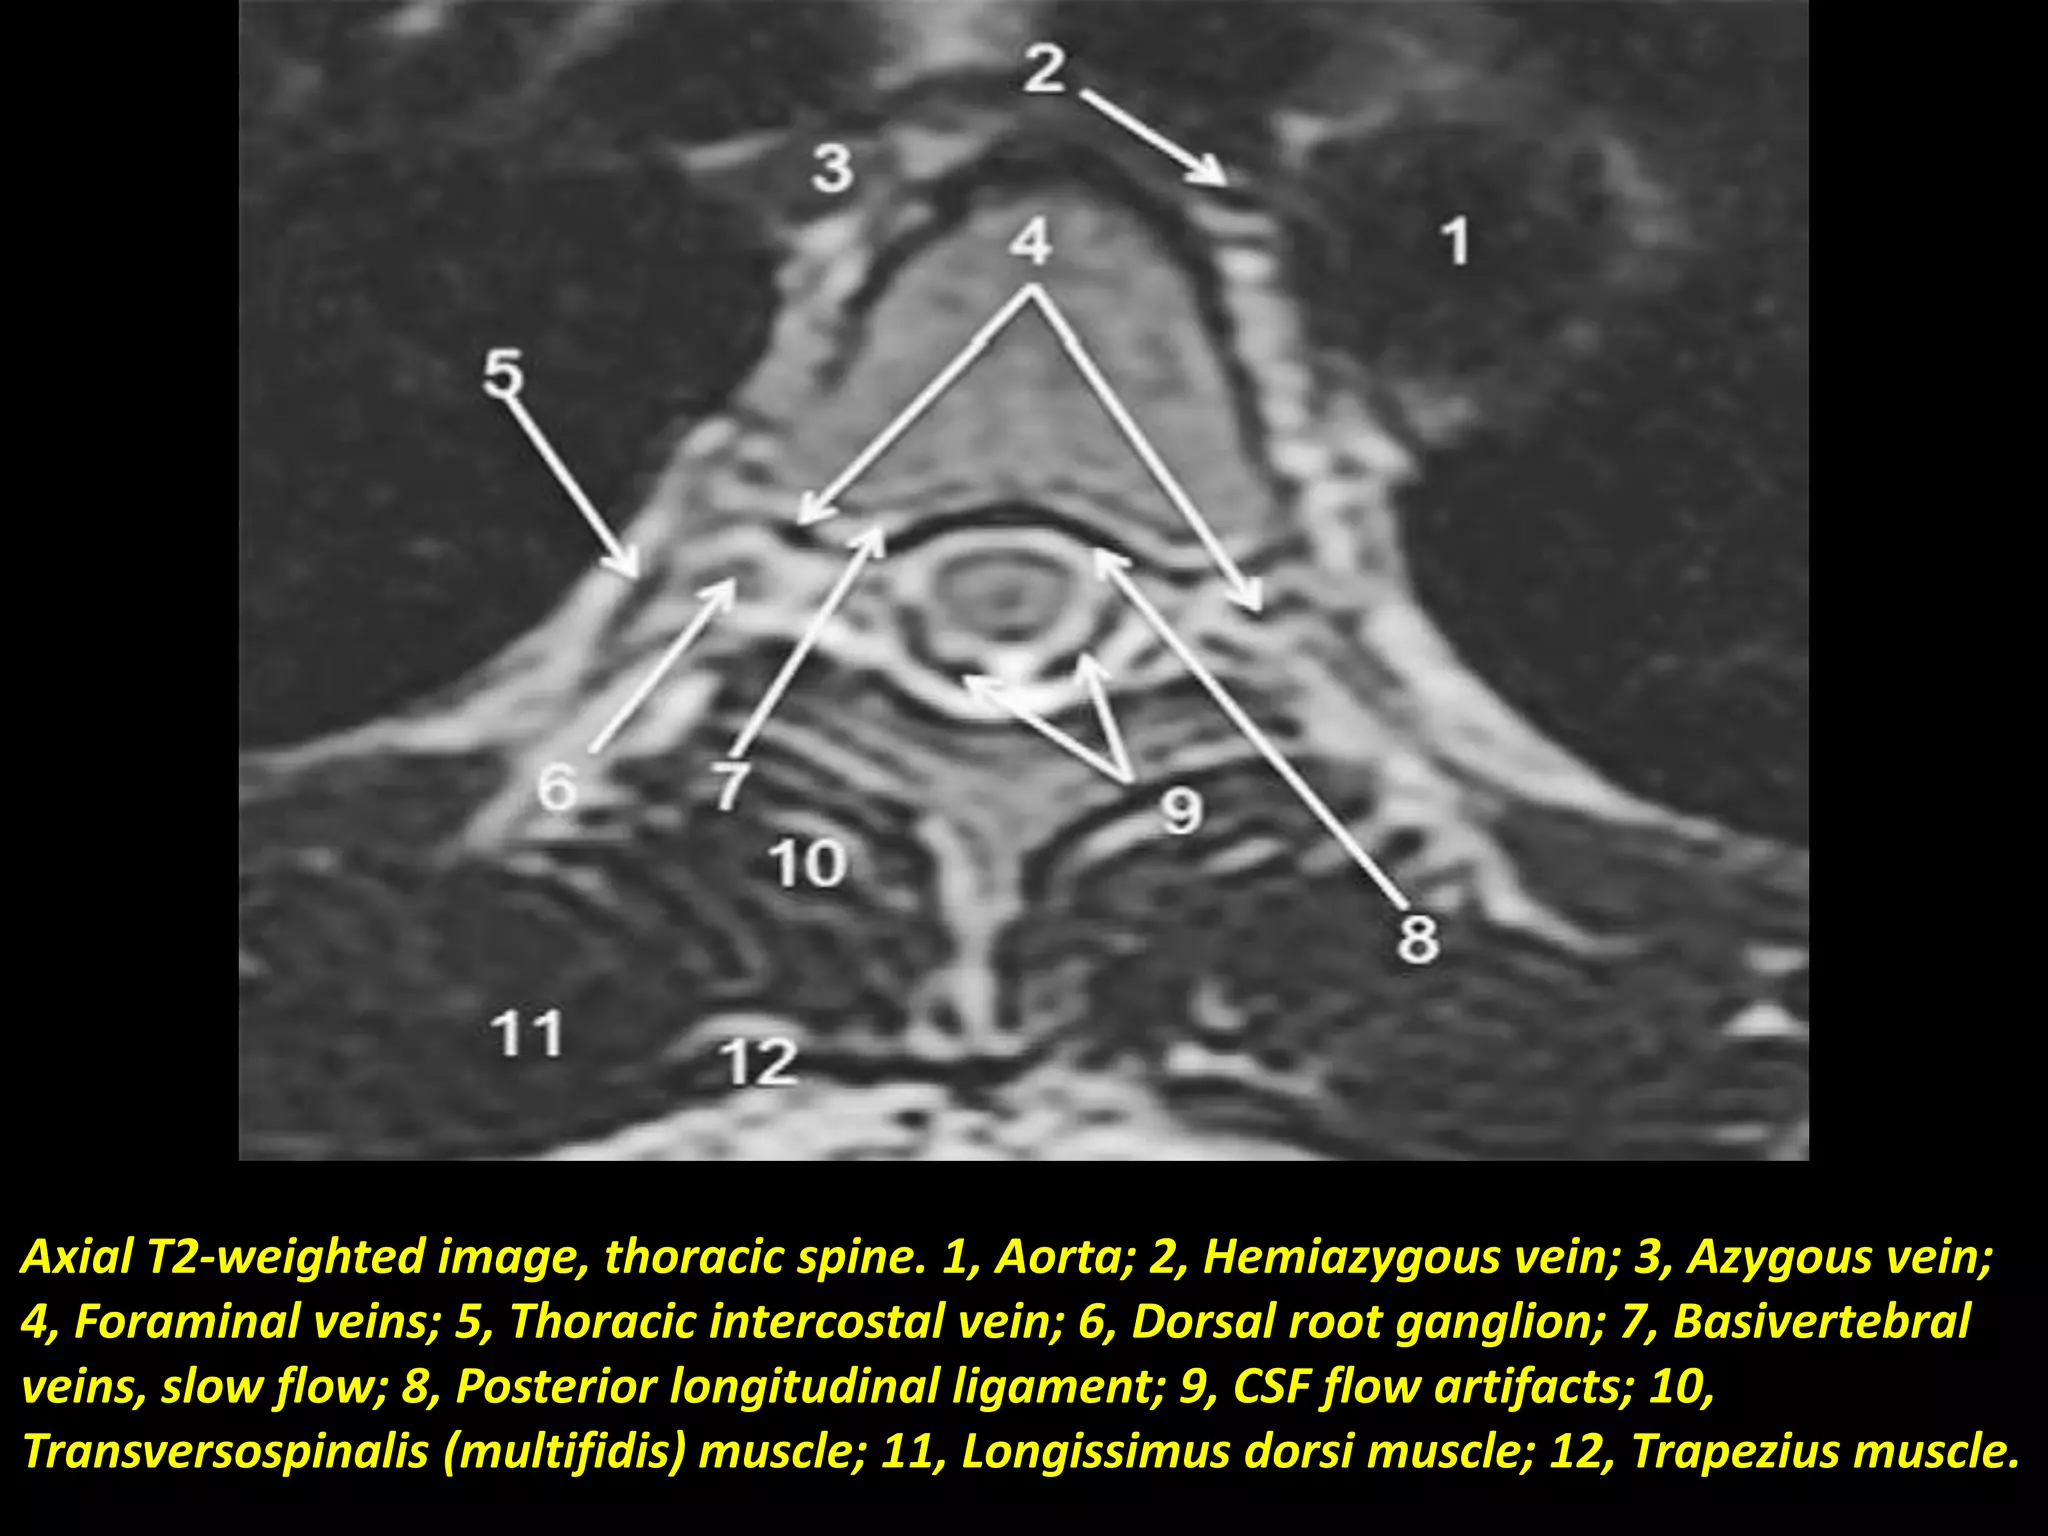

Axial T2-weighted image, thoracic spine. 1, Aorta; 2, Hemiazygous vein; 3, Azygous vein;

4, Foraminal veins; 5, Thoracic intercostal vein; 6, Dorsal root ganglion; 7, Basivertebral

veins, slow flow; 8, Posterior longitudinal ligament; 9, CSF flow artifacts; 10,

Transversospinalis (multifidis) muscle; 11, Longissimus dorsi muscle; 12, Trapezius muscle.

Axial T2-weighted image,thoracic spine. 1, Aorta; 2, Hemiazygous vein; 3, Azygous vein; 4, Foraminal veins; 5, Thoracic intercostal vein; 6, Dorsal root ganglion; 7, Basivertebral veins, slow flow; 8, Posterior longitudinal ligament; 9, CSF flow artifacts; 10, Transversospinalis (multifidis) muscle; 11, Longissimus dorsi muscle; 12, Trapezius muscle.